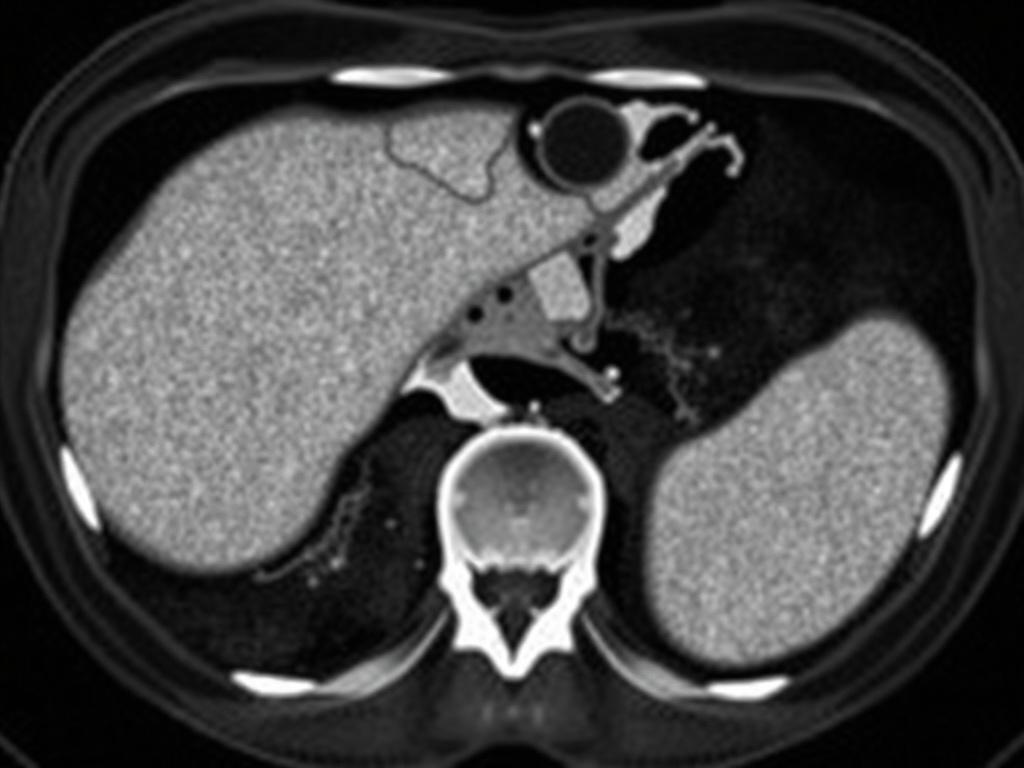

Компьютерная томография печени с контрастом — это серия рентгеновских снимков, объединённых в трёхмерную картинку, снятая после введения контрастного вещества. Контраст помогает выделить сосуды и патологические образования, делая картинку информативнее, чем обычная неусиленная томография. Больше информации о том какая на КТ печени с контрастом цена Москва, можно узнать пройдя по ссылке.

Принцип простой: контраст аккумулируется в тканях по-разному, и плотность этих участков меняется на изображениях. По этим изменениям врач судит о наличии опухолей, метастазов, абсцессов и других проблемах.

Фазы важны: артериальная, портальная и отсроченная показывают разные свойства тканей. Например, некоторые опухоли ярче видны в артериальной фазе, а другие — в портальной.

| Фаза | Время после введения контраста | Что видно |

|---|---|---|

| Неусиленная | до введения | базовая плотность тканей, кальцинаты, кровоизлияния |

| Артериальная | 20–30 секунд | гиперваскулярные опухоли, артериальные аномалии |

| Портальная | 60–70 секунд | метастазы, большинство очагов печени |

| Отсроченная (венозная) | 3–5 минут | склонность контраста задерживаться в тканях, рубцы |

Таблица помогает понять, почему врач просит именно такой протокол съёмки. Каждая фаза дополняет картину и уменьшает риск пропуска важной детали.